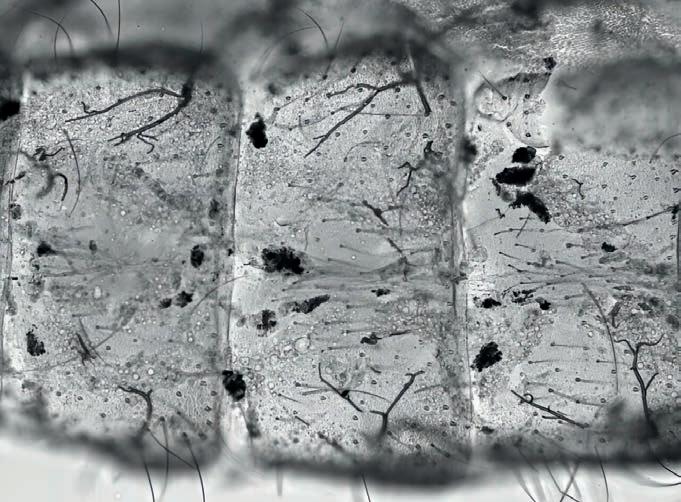

Aumento

dos mosquitos, enfraquecendo seus sistemas imunológicos. Como na visão aproximada do abdômen de um mosquito, que contém depósitos escuros de melanina